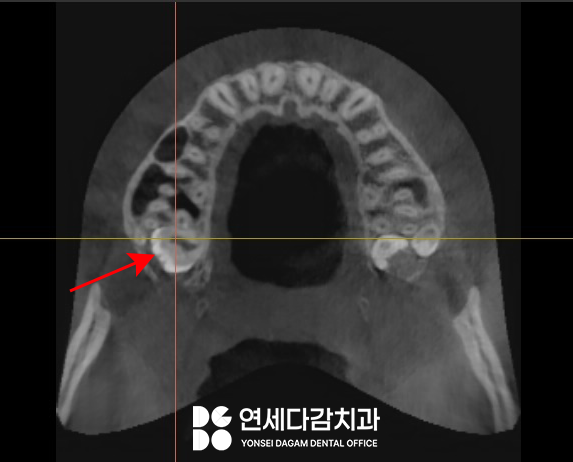

부분 맹출 된 치아를

먼저 접근하여 뺀 뒤에

노출된 공간을 활용하여

깊숙이 매복된 제3대구치에

접근하였습니다.

아주 깊은 상악 매복 사랑니의 경우

발치 중 천공을 피하기 매우 어렵고,

이 케이스에서도 작은 천공이 발생했습니다.

하지만 적절하게 처치만 한다면

문제가 되지 않습니다.

즉시 콜라겐 성분의

지혈제를 천공 부위에 삽입하여

상악동을 폐쇄하였습니다.